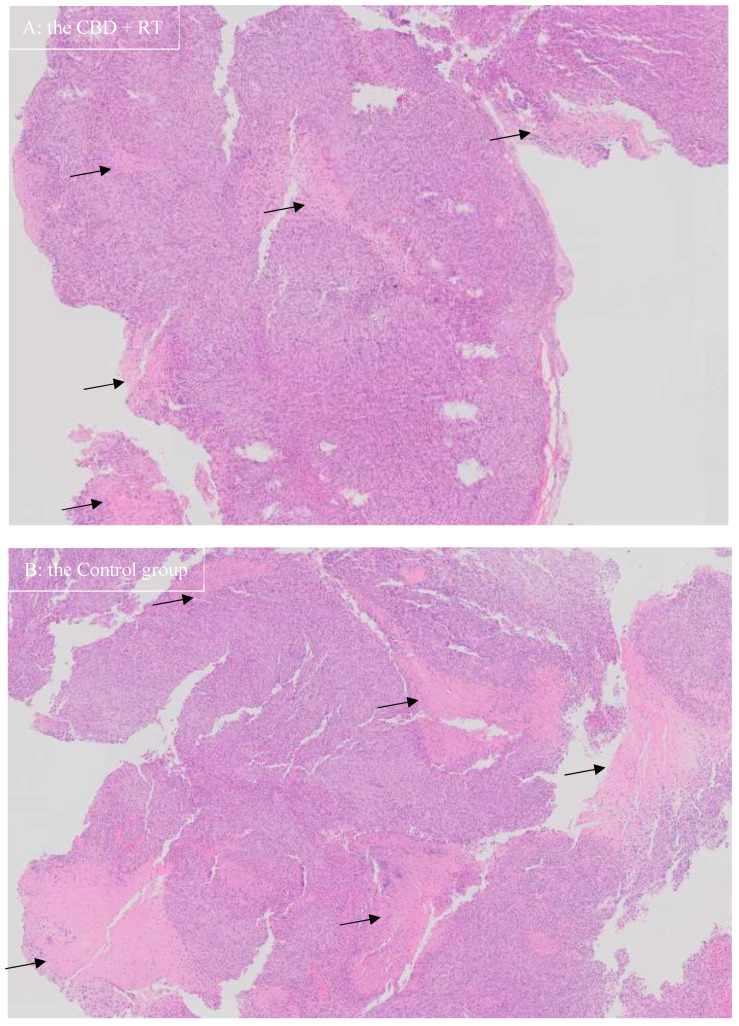

For histopathological examination, representative H&E microscopic images are shown in Figure 3. The appearance of the neoplasia looked similar among groups; however, necrotic areas appeared more pronounced in Group C than the other groups where CBD + RT group showed the mildest necrosis. The percentage of Ki-67-positive cells over total nuclei cells (%) and the number of positive cells (cells/μm2) are shown in Table 3. Representative images of Ki-67 staining are shown in Figure 4. In Group C, positive nuclei mean (median) was 0.235 (0.177)% and 15.364 (10.866)/μm2 in the neoplasm and 0.051 (0.051)% and 1.427 (1.420)/μm2 in non-diseased brain tissue. In the CBD group, positive nuclei mean (median) was 1.124 (0.774) % and 62.336 (47.833)/μm2 in the neoplasm and 0.620 (0.342)% and 16.086 (9.070)/μm2 in non-diseased brain tissue. In the RT group, positive nuclei mean (median) was 1.590 (1.282)% and 95.587 (64.529)/μm2 in the neoplasm and 0.485 (0.370)% and 11.927 (8.374)/μm2 in non-diseased brain tissue. In the CBD + RT group, positive nuclei mean (median) was 0.511 (0.531)% and 27.999 (27.658)/μm2 in the neoplasm and 0.218 (0.128)% and 5.009 (3.071)/μm2 in non-diseased brain tissue.

In the present study, the percentage of Ki-67-positive cells over total nuclei cells (%) and the number of positive cells (cells/μm2) were calculated. A meta-analysis of human glioma in 2015 revealed that Ki-67 expression might be a predictive factor for poor prognosis in glioma patients [ref. 39]. Although the glioma cell line was the same in the present study, it was assumed that Ki-67-positive cells in Group C would be greater than in the other groups; however, the percentage of Ki-67-positive cells over total nuclei cells (%) and the number of positive cells (cells/μm2) in Group C were fewer than in the other groups. The reason for this is not known, but since the J3TBG glioma cell line is known to behave aggressively, there might be a contribution of more necrotic tumor cells generated in Group C than in the treatment groups (CBD, RT, CBD + RT groups), resulting in fewer percentage of Ki-67-positive cells and fewer number of positive cells (cells/μm2), as shown in Figure 3. Among treatment groups, the RT + CBD group demonstrated the lowest values for both the percentage and number of Ki-67-positive cells, which may represent the usefulness of Ki-67 for treatment evaluation. Further studies are required to assess utility of Ki-67 for the J3TBG glioma cell line.